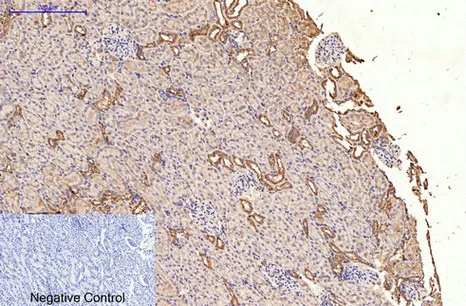

LC3A(5G10)Mouse Monoclonal Antibody

Cat: AMM13240

Size1:50μL Price1:$118

Size2:100μL Price2:$220

Size3:200μL Price3:$380

Application:WB,IF-P,IF-F,ICC/IF,IHC-P

Reactivity:Human,Rat,Mouse

Conjugate:Unconjugated

Optional conjugates: Biotin, FITC (free of charge). See other 26 conjugates.

Gene Name:MAP1LC3A